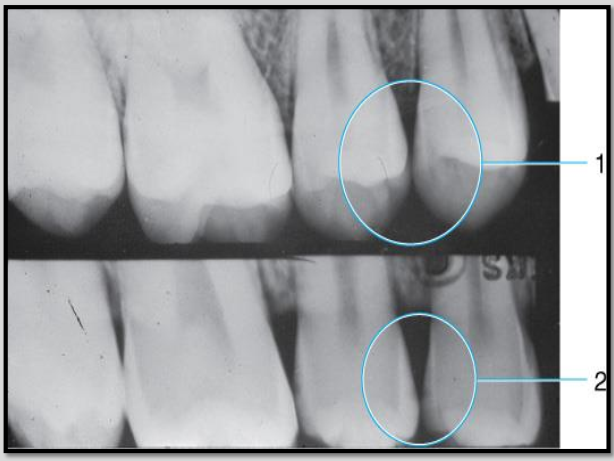

3 Criteria for a bite-wing exposuresÂ

What does #1 show?

#1 shows INCORRECT vertical angulation

it is over angulated thus obstructing the interproximal view of the lesion

#2 shows CORRECT vertical angulation

interproximal caries now visible on the radiograph.

**vertical angulation = tilting PID up or down